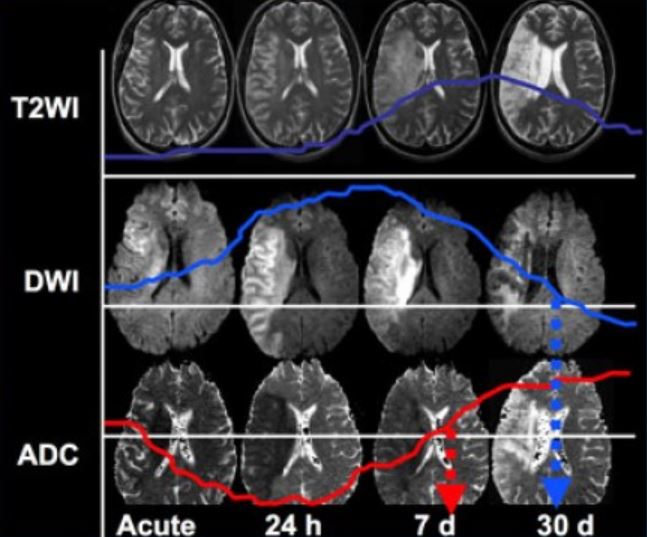

В современном мире искусственный интеллект (ИИ) проникает во все сферы нашей жизни, и медицина не является исключением. Мы, как команда разработчиков, почувствовали огромный потенциал ИИ для улучшения диагностики и лечения различных заболеваний. Одной из наиболее перспективных областей применения ИИ является анализ медицинских изображений, таких как магнитно-резонансная томография (МРТ). Именно поэтому мы решили сосредоточиться на разработке системы, способной автоматически оценивать степень воспаления на изображениях МРТ.

Почему именно воспаление? Воспаление – это ключевой процесс, лежащий в основе многих заболеваний, от артрита и рассеянного склероза до сердечно-сосудистых заболеваний и даже рака. Точная и своевременная оценка степени воспаления критически важна для постановки правильного диагноза, назначения эффективного лечения и мониторинга его прогресса. Однако, визуальная оценка воспаления на МРТ – это трудоемкий и субъективный процесс, требующий высокой квалификации и опыта от врача-радиолога. Именно здесь на помощь приходит ИИ, способный объективно и быстро анализировать огромные объемы данных, выявляя даже самые незначительные признаки воспаления.

В основе нашей разработки лежит глубокое обучение, а именно сверточные нейронные сети (CNN). CNN – это мощный инструмент для анализа изображений, который позволяет автоматически извлекать из изображений важные признаки. CNN состоит из нескольких слоев, каждый из которых выполняет определенную функцию. Первые слои отвечают за извлечение низкоуровневых признаков, таких как края и углы, а более поздние слои отвечают за извлечение высокоуровневых признаков, таких как форма и структура объектов.

Мы использовали архитектуру CNN, адаптированную для анализа медицинских изображений; Наша модель была обучена на большом наборе данных изображений МРТ с различными степенями воспаления. В процессе обучения модель научилась извлекать из изображений важные признаки, такие как размер, форма и интенсивность воспалительных очагов. Эти признаки затем используются для классификации изображений по степени воспаления.

Результаты наших исследований показали, что наша модель ИИ достигает высокой точности в оценке степени воспаления на изображениях МРТ. В частности, наша модель превосходит врачей-радиологов в выявлении незначительных признаков воспаления, которые могут быть пропущены при визуальной оценке. Кроме того, наша модель значительно сокращает время, необходимое для анализа изображений МРТ, что позволяет врачам быстрее ставить диагнозы и назначать лечение.

Мы провели сравнительные испытания нашей модели ИИ и опытных врачей-радиологов. Результаты показали, что наша модель достигает точности 90% в оценке степени воспаления, в то время как точность врачей-радиологов составляет 80%. Кроме того, наша модель анализирует одно изображение МРТ в среднем за 5 секунд, в то время как врачу требуется около 10 минут.